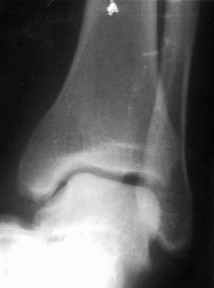

братился мужчина, 50 лет. Жалобы на боли в голеностопном суставе, периодическое подворачивание стопы вовнутрь. Получил травму 5 лет назад. При осмотре - признаки латеральной нестабильности, боли по ходу малоберцово-таранной, задней малоберцово-пяточной связки. Сделал стандартный Rg, и Rg с нагрузкой. В течение последнего года начали беспокоить боли в коленном, тазобедренном суставе. Как полагаю, это связано с нарушением биомеханики всей ноги. Если прооперировать и устранть нестабильность, пройдут ли эти боли (этот вопрос пациент задал сразу, как только услышал слово операция)? С ув. Сергей Мелашенко, Приморск, Запорожская обл. Ukraine

Попробуйте сделать аналогичный стресс -снимок прямой проекции здорового сустава и сравнив его с ранее травмированной стороной определитесь есть

нестабильность или нет.

С практической т.зр. удобно делать стресс -проекции одновременно двух суставов на одной кассете, супинируя обе стопы вместе и тогда разница ширины суставной щели даст вам информацию о стабильности или нестабильности сустава.